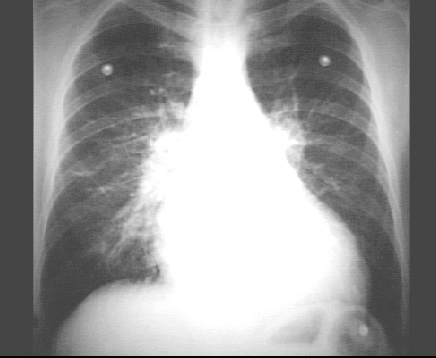

PA view

The PA view demonstrates the enlarged left ventricle as an increase in the inferolateral cardiac border, associated with an increased cardiothoracic ratio. Pulmonary congestion is demonstrated by a diffuse increase in vascular markings throughout the lungs. Prominent pulmonary arteries are also seen in the hilar region.

Note the electrode shadows in this patient whose chest X rays were taken while being monitored.